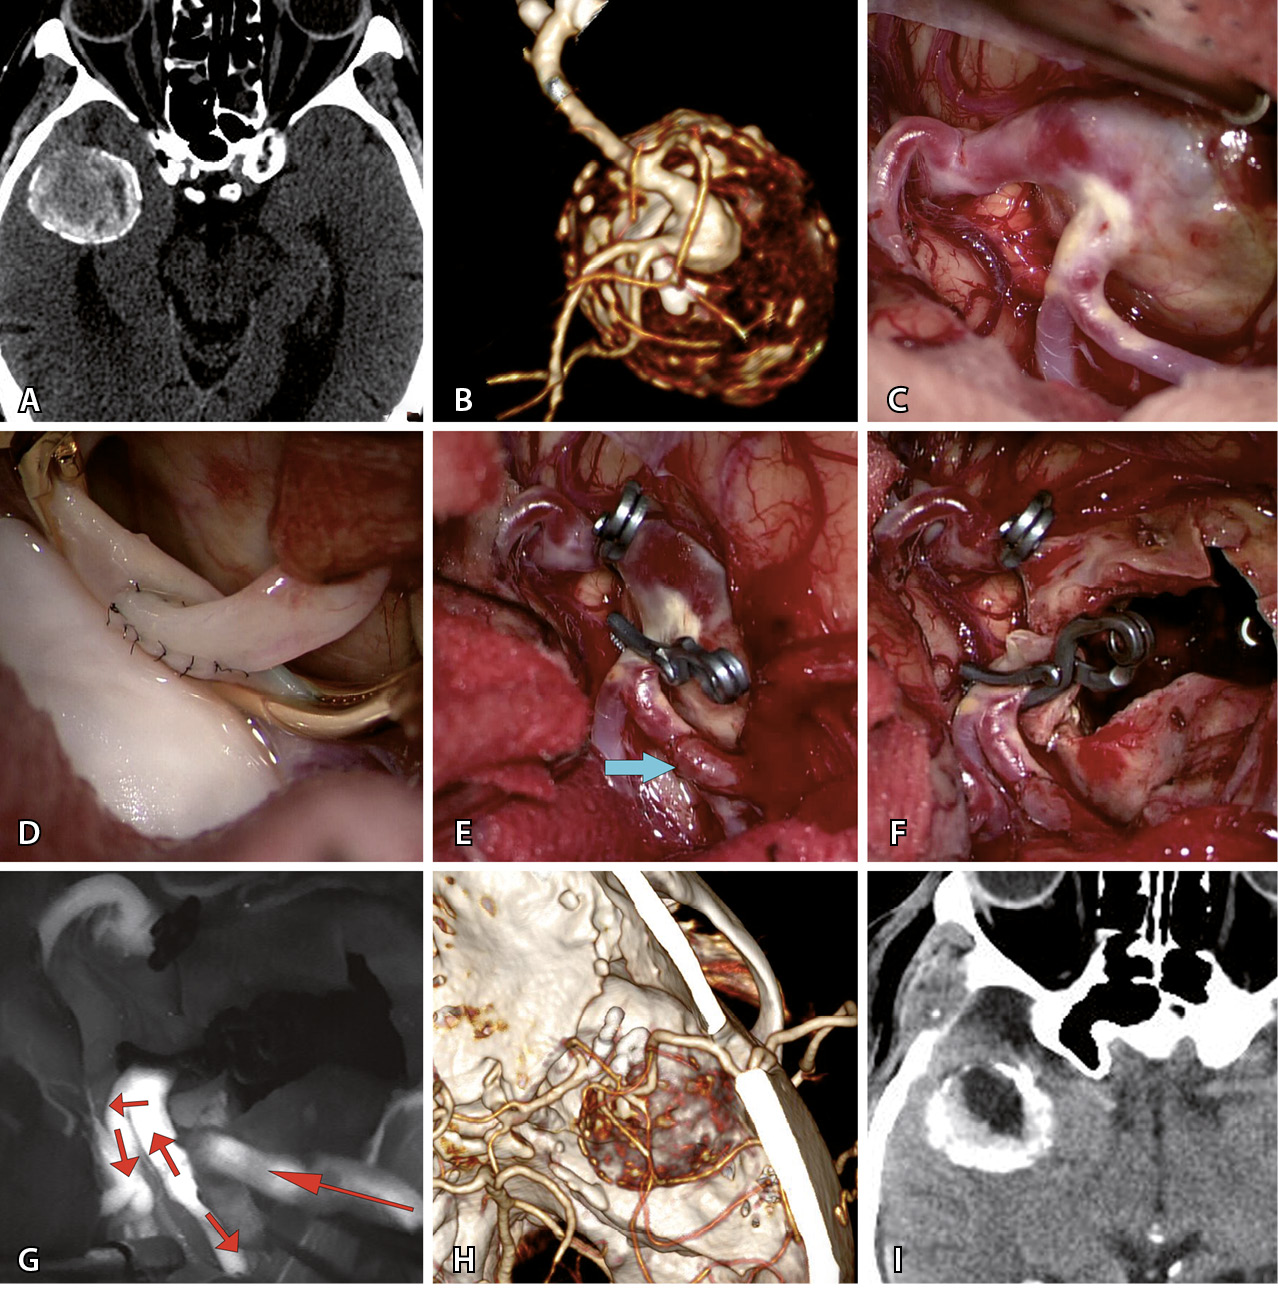

Операции с созданием байпаса сделаны в 19 случаях. Байпас перед треппингом аневризмы выполнен у 10 пациентов (в 8 случаях после треппинга проведена тромбэктомия). В 3 случаях при фузиформных гигантских аневризмах проведено проксимальное клипирование с целью создания возможности ретроградного кровоснабжения ветвей, выходящих из аневризмы. У 4 пациентов была реваскуляризация одной из М2-ветвей, где гигантская аневризма клипирована вместе с устьем данной ветви. В 2 случаях потребность в анастомозе возникла как экстренная мера вследствие тромбоза одной из ветвей СМА после КШ. Наиболее частым (n = 15) байпасом был микроанастомоз между М2–М4 ветвью СМА и поверхностной височной артерией (ПВА). Пример представлен на рис. 2. Микроанастомозы с двумя ветвями ПВА выполнены в 6 случаях. Высокопоточный байпас между наружной сонной артерией и М2-сегментом СМА с использованием графта лучевой артерии выполнен в 3 случаях при гигантской аневризме М1-сегмента. В 1 наблюдении произведена местная реимплантация одной М2-ветви в другую.

Рис. 2. Треппинг с тромбэктомией гигантской фузиформной частично тромбированной аневризмы М2-сегмента средней мозговой артерии (СМА) после создания экстра-интракраниального микроанастомоза у пациента Т., 69 л. А – компьютерная томография до операции: определяется гигантская частично тромбированная аневризма правой СМА. Б – компьютерная томографическая ангиография (3D) до операции: видна функционирующая часть фузиформной частично тромбированной аневризмы М2-сегмента правой СМА. В – интраоперационное фото: вид аневризмы после препаровки сильвиевой щели. Г – анастомоз между поверхностной височной артерией и М2-сегментом СМА. Д – треппинг аневризмы (стрелкой указан анастомоз). Е – вид аневризмы после тромбэктомии из ее полости. Ж – флюоресцентная видеоангиография: видно хорошее контрастирование шунта через анастомоз и заполнение М2-ветвей (стрелками указано направление кровотока). З – компьютерная томографическая ангиография (3D) после операции: аневризма не контрастируется и хорошо заполняется экстра-интракраниальный анастомоз. И – компьютерная томография головы после операции